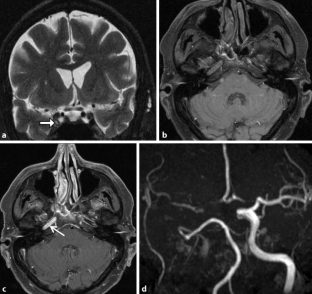

Abb. 1